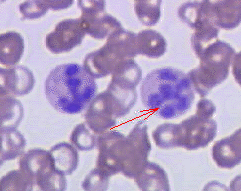

Μεγαλοβλαστικη αναιμία

Είναι ένας τύπος αναιμίας που εμφανίζεται όταν ο οργανισμός δεν μπορεί να παράγει φυσιολογικά ερυθρά αιμοσφαίρια λόγω διαταραχής στη σύνθεση του DNA. Ως αποτέλεσμα, στον μυελό των οστών δημιουργούνται μεγάλα και ανώριμα κύτταρα που ονομάζονται «μεγαλοβλάστες».